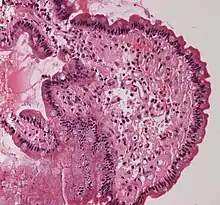

Coloration histologique

En milieu clinique, les maladies amyloïdes sont généralement identifiées par un changement d'intensité de fluorescence de colorants aromatiques plans tels que la thioflavine T, le rouge Congo ou le NIAD-4[68]. En général, cela est attribué au changement environnemental, car ces colorants s'intercalent entre des brins bêta pour confiner leur structure [69]. La positivité du rouge Congo reste la référence en matière de diagnostic de l’amylose. En général, la liaison du rouge Congo aux plaques amyloïdes produit une biréfringence vert pomme typique lorsqu'elle est observée sous une lumière polarisée croisée. Récemment, l'amélioration significative du rendement quantique de fluorescence de NIAD-4 a été exploitée pour l'imagerie par fluorescence à super-résolution de fibrilles amyloïdes[70] et d'oligomères[71]. Pour éviter une coloration non spécifique, d'autres colorations histologiques, telles que la coloration à l'hématoxyline et à l'éosine, sont utilisées pour éteindre l'activité des colorants à d'autres endroits, tels que le noyau, où le colorant pourrait se lier. La technologie moderne des anticorps et l'immunohistochimie ont facilité des colorations spécifiques, mais cela peut souvent poser problème car les épitopes peuvent être dissimulés dans le repli amyloïde. En général, une structure de protéine amyloïde a une conformation différente de celle reconnue par l'anticorps.